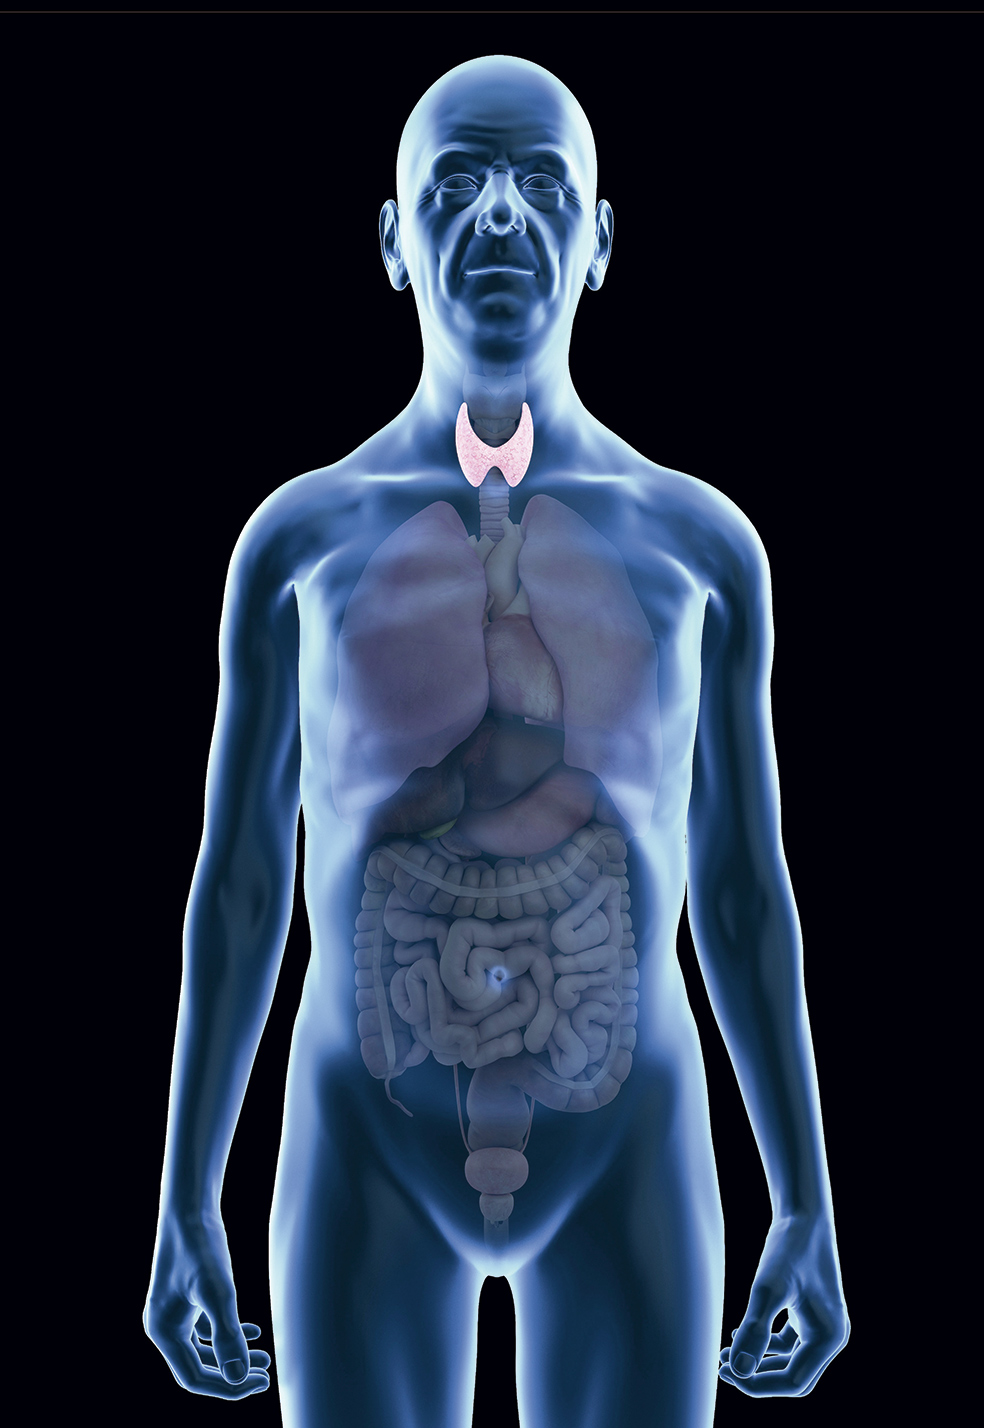

En estos momentos se considera que un 10 por ciento de la población española padece una enfermedad del tiroides (aunque se estima que una gran parte no ha sido diagnosticada). En la mayoría de los casos –un 91 por ciento–, esta disfunción se debe a que su actividad ha disminuido, lo que provoca una cantidad insuficiente de hormona; es lo que conocemos como hipotiroidismo.

El 9 por ciento restante se debe a la situación contraria: el tiroides está demasiado activo y produce demasiada hormona. Es el hipertiroidismo. Ambas son las disfunciones más comunes, muy por encima de los casos de bocio o de cáncer de tiroides. Y todas ellas son, por causas que no terminan de estar claras, mucho más prevalentes en mujeres.

Viendo las cifras, vemos claro que el foco adonde se dirigen todas las miradas es al hipotiroidismo, disfunción que padecen alrededor de 700.000 personas en España. ¿Hay realmente más que antes? «No está claro. Pero es evidente que se diagnostica mucho más», sugiere la doctora Navarro.